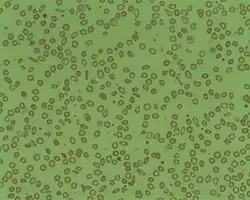

| Microcytosis is the presence of red cells that are smaller than normal. Normal adult red cell has a diameter of 7.2 µm. Microcytes are common seen in with hypochromia in iron-deficiency anaemia, thalassaemia trait, congenital sideroblastic anaemia and sometimes in anaemia of chronic diseases. | |

Microcytic anaemia is any of several types of anemia characterized by smaller than normal red blood cells (called microcytes). The normal mean corpuscular volume of a red blood cell is approximately 80–100 fL. When the MCV is <80 fL, the red cells are described as microcytic. MCV is the average red blood cell size. The main causes of microcytic anemia are iron-deficiency, lead poisoning, thalassemia, and anemia of chronic disease.

In microcytic anemia, the red blood cells (erythrocytes) contain less hemoglobin and are usually also hypochromic, meaning that the red blood cells appear paler than usual. This can be reflected by a low mean corpuscular hemoglobin concentration (MCHC), a measure representing the amount of hemoglobin per unit volume of fluid inside the cell; normally about 320–360 g/L or 32–36 g/dL. Typically, therefore, anemia of this category is described as "microcytic, hypochromic anemia".

In theory, the three most common microcytic anemias (iron deficiency anemia, anemia of chronic disease, and thalassemia) can be differentiated by their red blood cell (RBC) morphologies. Anemia of chronic disease shows unremarkable RBCs, iron deficiency shows anisocytosis, anisochromia and elliptocytosis, and thalassemias usually demonstrate target cells. Basophilic stippling is one morphologic finding of thalassemia which does not appear in iron deficiency or anemia of chronic disease. The patient should be in an ethnically at-risk group (e.g. Greek, Cypriot, Turkish, North African) and the diagnosis is not confirmed without a confirmatory method such as hemoglobin HPLC, H body staining, molecular testing or another reliable method. Coarse basophilic stippling occurs in other cases as seen in Table 1.[11]